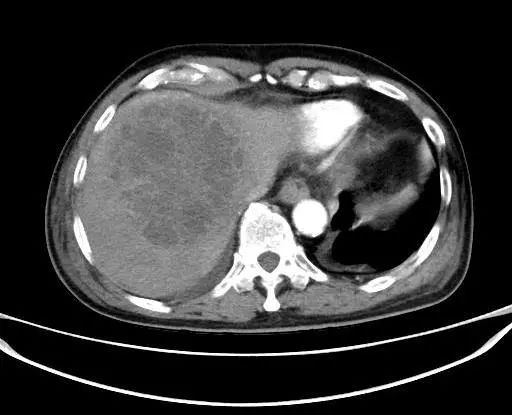

经过数天抗感染治疗,ct复查示脓肿持续增大,白细胞居高不下,肝肾功能出现异常,为了防止病情进一步发展,普外科与超声医学科陈曼主任会诊后认为急需进行超声引导下肝脓肿穿刺置管引流,需要对抽出的脓液进行细菌培养和药物敏感试验,以便选用有效的抗生素进行治疗,同时置管引流脓液。

术前对病灶进行充分评估,并做了超声造影,肝脓肿较成人拳头略大,內见较多的分隔。

于是,我们决定进行肝脓肿的置管引流。同时,患者的核酸报告结果也为阴性,在封控的情况下,我们第一次在身穿防护服及三层手套的条件下进行手术,抽出脓液20ml,并顺利完成了置管引流,过程顺利,病人安全。